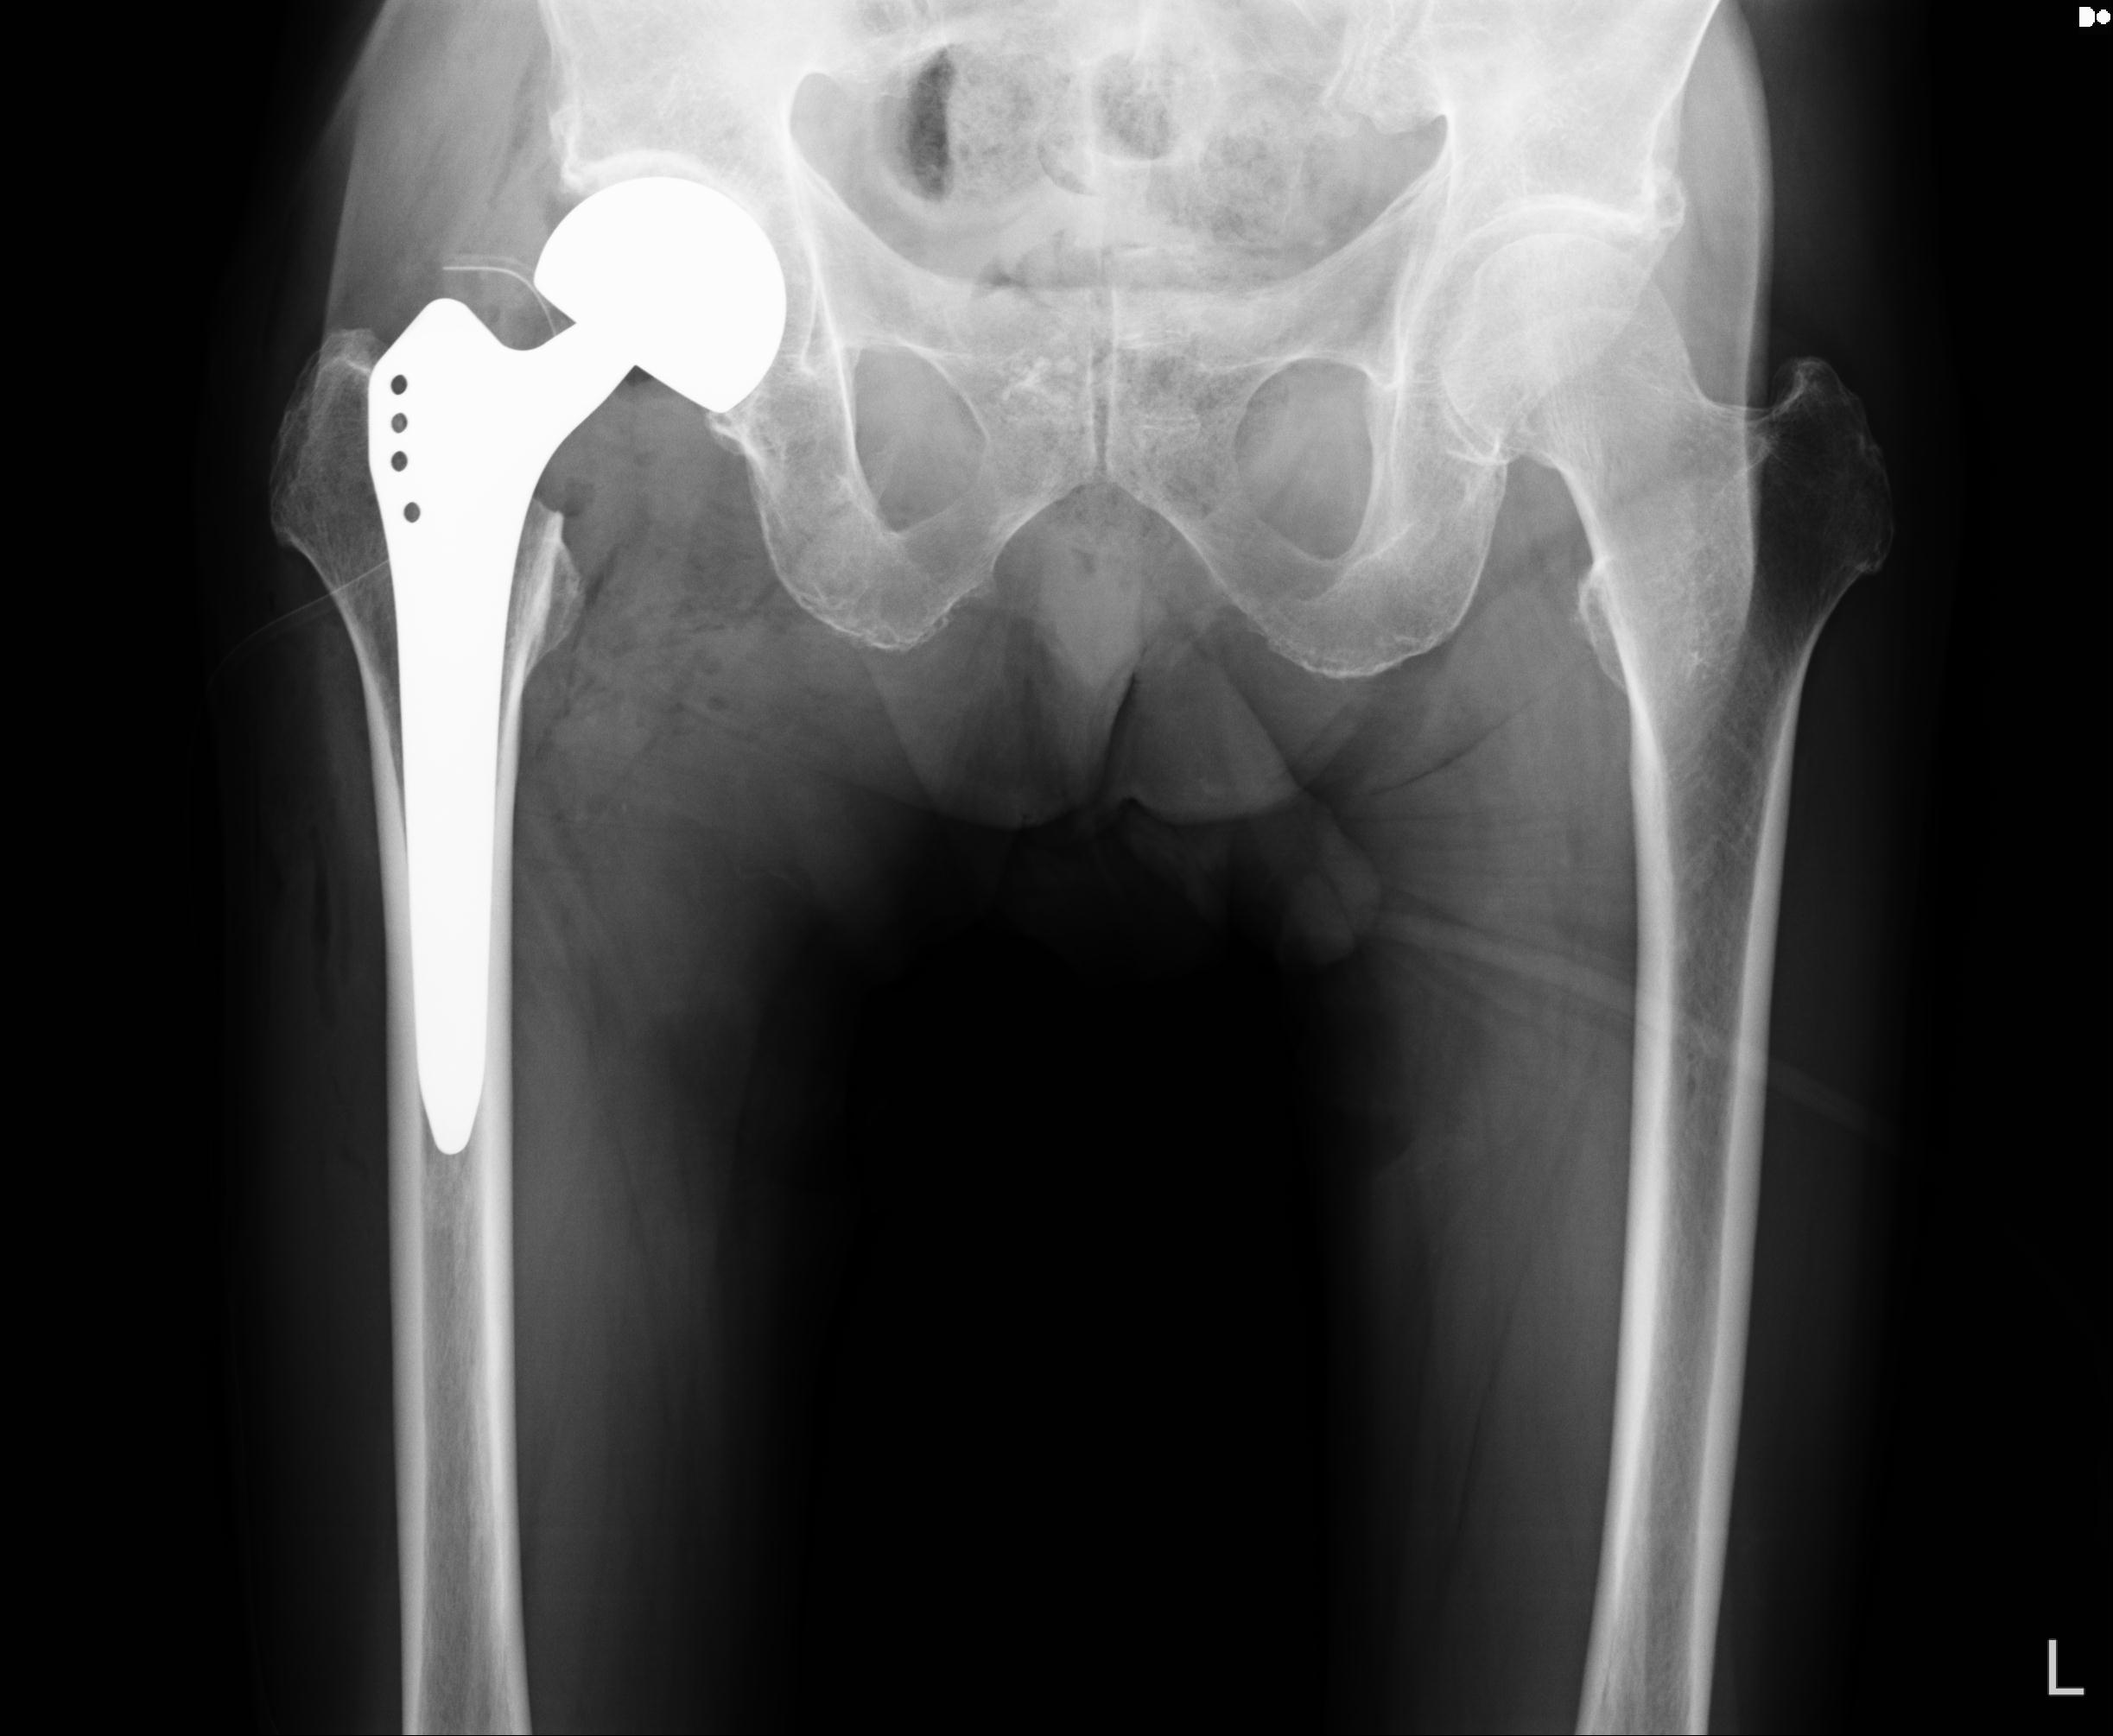

82084 1/14 1/20 股関節 2R 78歳男性 右人工骨頭